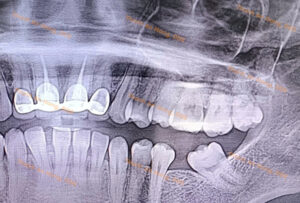

Dì Gân Răng Cối Lớn Hàm Dưới